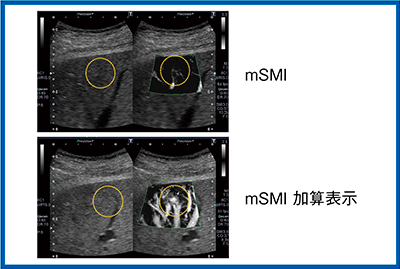

肝細胞がん:異所性再発

SMIは淡い微細な変化の把握に有用であるが,ROIの背景のBモードを消して血管構築を見るため,超音波検査の基本であるBモードも同時に観察できる2画面表示を推奨する。造影検査においても2画面表示とすることで,Bモードで腫瘍濃染を,SMIで不整血管を見ることができる。SMIを評価するタイミングとしては,門脈優位相と後血管相の間にSMI加算画像を取得している。従来の検査プロトコールを妨げることなく,腫瘍部の血管構築を観察することができる(図5)。

このように,SMI造影はいつでもできる利点がある。しかし,肝がんの診断には,やはり造影剤のファーストパスが最適であり,ここでも2画面表示を推奨している。ファーストパスでは,Bモード造影で腫瘍が濃染される様子と,SMIでの複雑な腫瘍血管の観察が同時に可能となるからである。そして,前述したが,気泡を再度崩壊させることにより,Bモード造影の腫瘍濃染像と,血管構築の再確認ができる。